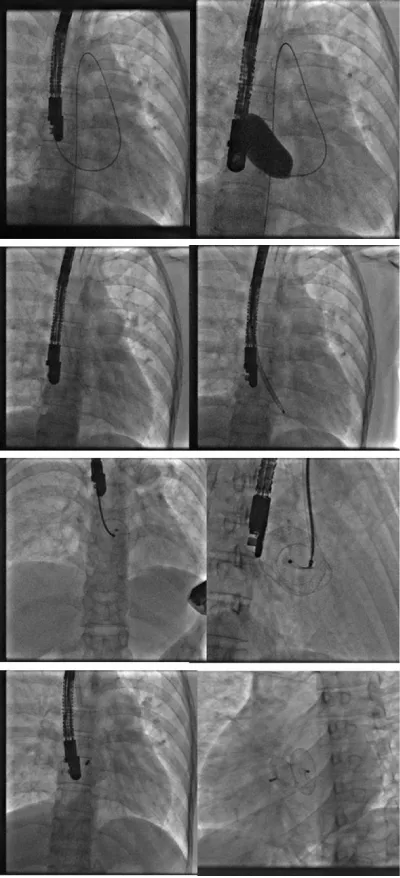

We decided then to put the wire in the aorta (through the ASD, then in the LA then LV and finally in the descending aorta as far as possible) in order to increase the support. From then on, the rest of the procedure became simple.

We reintroduced the calibration balloon giving a stretched ASD diameter of 23 mm (measurement by angiography and echocardiography TTE/TEE) fixing our choice on a 26 mm prosthesis which requires a septum height of 40 mm (26 + 2×7) that was exactly our patient’s septum height.

Then, we introduced the 12 Fr sheath from the internal jugular vein and prepared the prosthesis in its chamber as described earlier in this document.

The deployment and release of the prosthesis were done under angiographic and echocardiographic control (TTE/TEE).

For that, we started by putting the delivery system through the mitral valve in order to increase the support and stabilize the system, then we pushed the prosthesis till the end of its sheath and then we pulled back everything into the left atrium (to avoid trapping the prosthesis in the mitral cords) to deploy the distal disc, brought back into contact with the septum than the proximal disc to thus sandwich the septum between the two discs (Figure 3).

After confirming the correct positioning of the prosthesis and the absence of conflict with the mitral valve, the pulmonary veins, and the superior vena cava, we released successfully the Occluder by anti-clockwise rotation of its rod (Figure 4).